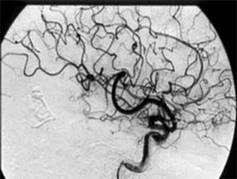

Коронарная ангиография является одной из процедур в кардиохирургии. Этот метод позволяет визуализировать такие изменения коронарных сосудов, как закупорку, сужение, повторное сужение, тромбоз или аневризматическое расширение просвета этих сосудов. Закупорка просвета артерий приводит к возникновению инфаркта миокарда, который может быть остановлен (в условиях специально оборудованного стационара) благодаря применению тромболитической терапии (рис.2) и/или установки стента (рис.3). Сейчас простая процедура коронарной катетеризации занимает не более 5-8 минут, при частоте осложнений 0,1%. Стентирование - весьма эффективный метод, во время выполнения ангиопластики при надувании баллончика на нем находится стент – цилиндрической формы каркасная проволока, которая расширяет стенозированный участок сосуда и не позволяет просвету артерии сужаться в дальнейшем. (Рис.2.) На стент может быть нанесено лекарственное вещество, способствующее эпителизации и предотвращающее тромбообразование.

Рис.2 Тромбированная артерия (1). Та же артерия после тромболизиса (2)

Рис.3

Ангиографическое изображение до (слева) и после (справа) полную окклюзию правой коронарной артерии. Окклюзия характеризуется сужением, нехваткой коллатералей и отсутствием кальцификации. Было установлено 3 стента с лекарством (3.5 x 33, 3.5 x 33, and 3.5 x 23).